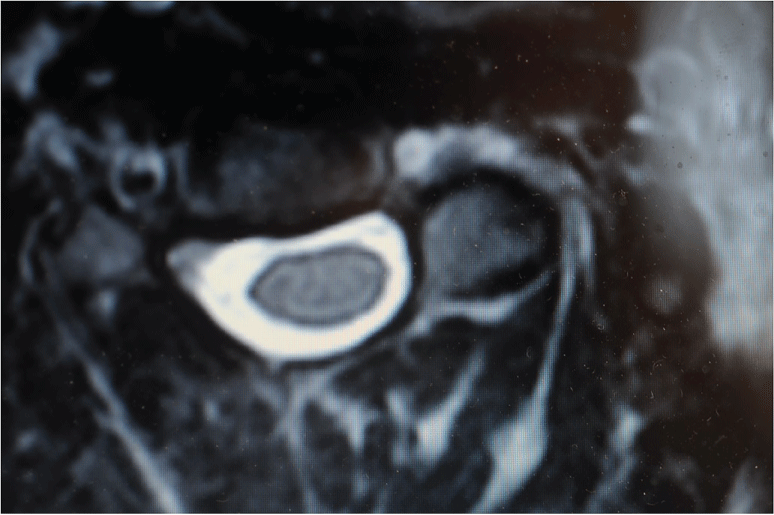

This patient study was approved by the Ethics Committee and was conducted following completion of the corresponding informed consent. A 10-year-old male patient in 2008 had consulted for a torticollis deformity that had originated during early childhood. This delay in first diagnosis is because patient is inmigrant and without diagnosis or previous treatment. Patient had classical deformities of torticollis: Shortening of SCM muscle, lateral inclination of the neck, smaller and higher eye, contralateral torsion with chin rising. Moreover, the patient also presented with a left-side facial deformity. The patient was not referred for any traumatic or infectious etiology of the oropharynx or for digestive or renal diseases. It was made a wide differential diagnosis, especially for to exclude nonmuscular causes of torticollis, presents in 18% of patients [1], Klippel-Feil anomalies (30%), posterior fossa tumors, syringomyelia or Arnold-Chiari malformation (51%) [1,2]. Additionally, neurologic exploration was done by a pediatric neurologist. Problems like dystonia, ataxia or abnormal deep tendon reflexes in upper and lower limbs did not exist. Also, osteocongenital neurological pathologies of the spinal cord and brain tumor were excluded by a pediatric neurologist. After these exclusions were made, we confirmed a diagnosis of inveterate congenital muscular torticollis. Preoperative studies, radiographic imaging, Computed Axial Tomography (CT) scans and Magnetic Resonance Imaging (MRI) of the cervical spine and skull (Figure1a, Figure 1b, Figure 2a, Figure 2b, Figure 3a, Figure 3b, Figure 4a, Figure 4b) highlighted Klippel-Feil Syndrome, fusion defects of the vertebral arches of the atlas, diastematomyelia and hypoplasia of the occipital condyles. CT images demonstrated, deformity of the anterior arch of the atlas was observed, consisting of hypoplasia of the right half and deformity and hypoplasia of the posterior arches C1 and C2 with concavity of the right posterior hemi-arch and convexity of the left arch, causing asymmetry of the spinal canal. Additionally, subluxation of the odontoid apophysis toward a right lateral mass of the atlas was observed (Figure 2a, Figure 3a). MRI showed deformity with extreme narrowing of the odontoid apophysis and irregular formation of the spinal canal with displacement of the spinal cord in the direction of the concavity of the torticollis (Figure 4a, Figure 4b). In 2009, unipolar distal tenotomy of the left SCM was performed, followed by orthotics and rehabilitation with notable improvement in cervical mobility but with minimal effect on facial asymmetry. In the 5-year postoperative CT and MRI, there were no significant changes in preoperative vertebral bone deformities, either visually or through the morphology of the spinal canal (Figure 5a, Figure 5b, and Figure 6).

Figure 6: Postoperative MR-scanning (5 years) remained unchanged: Spinal canal deformity and the asymmetric position of the spinal cord towards the concavity of the torticollis are noted. View Figure 6